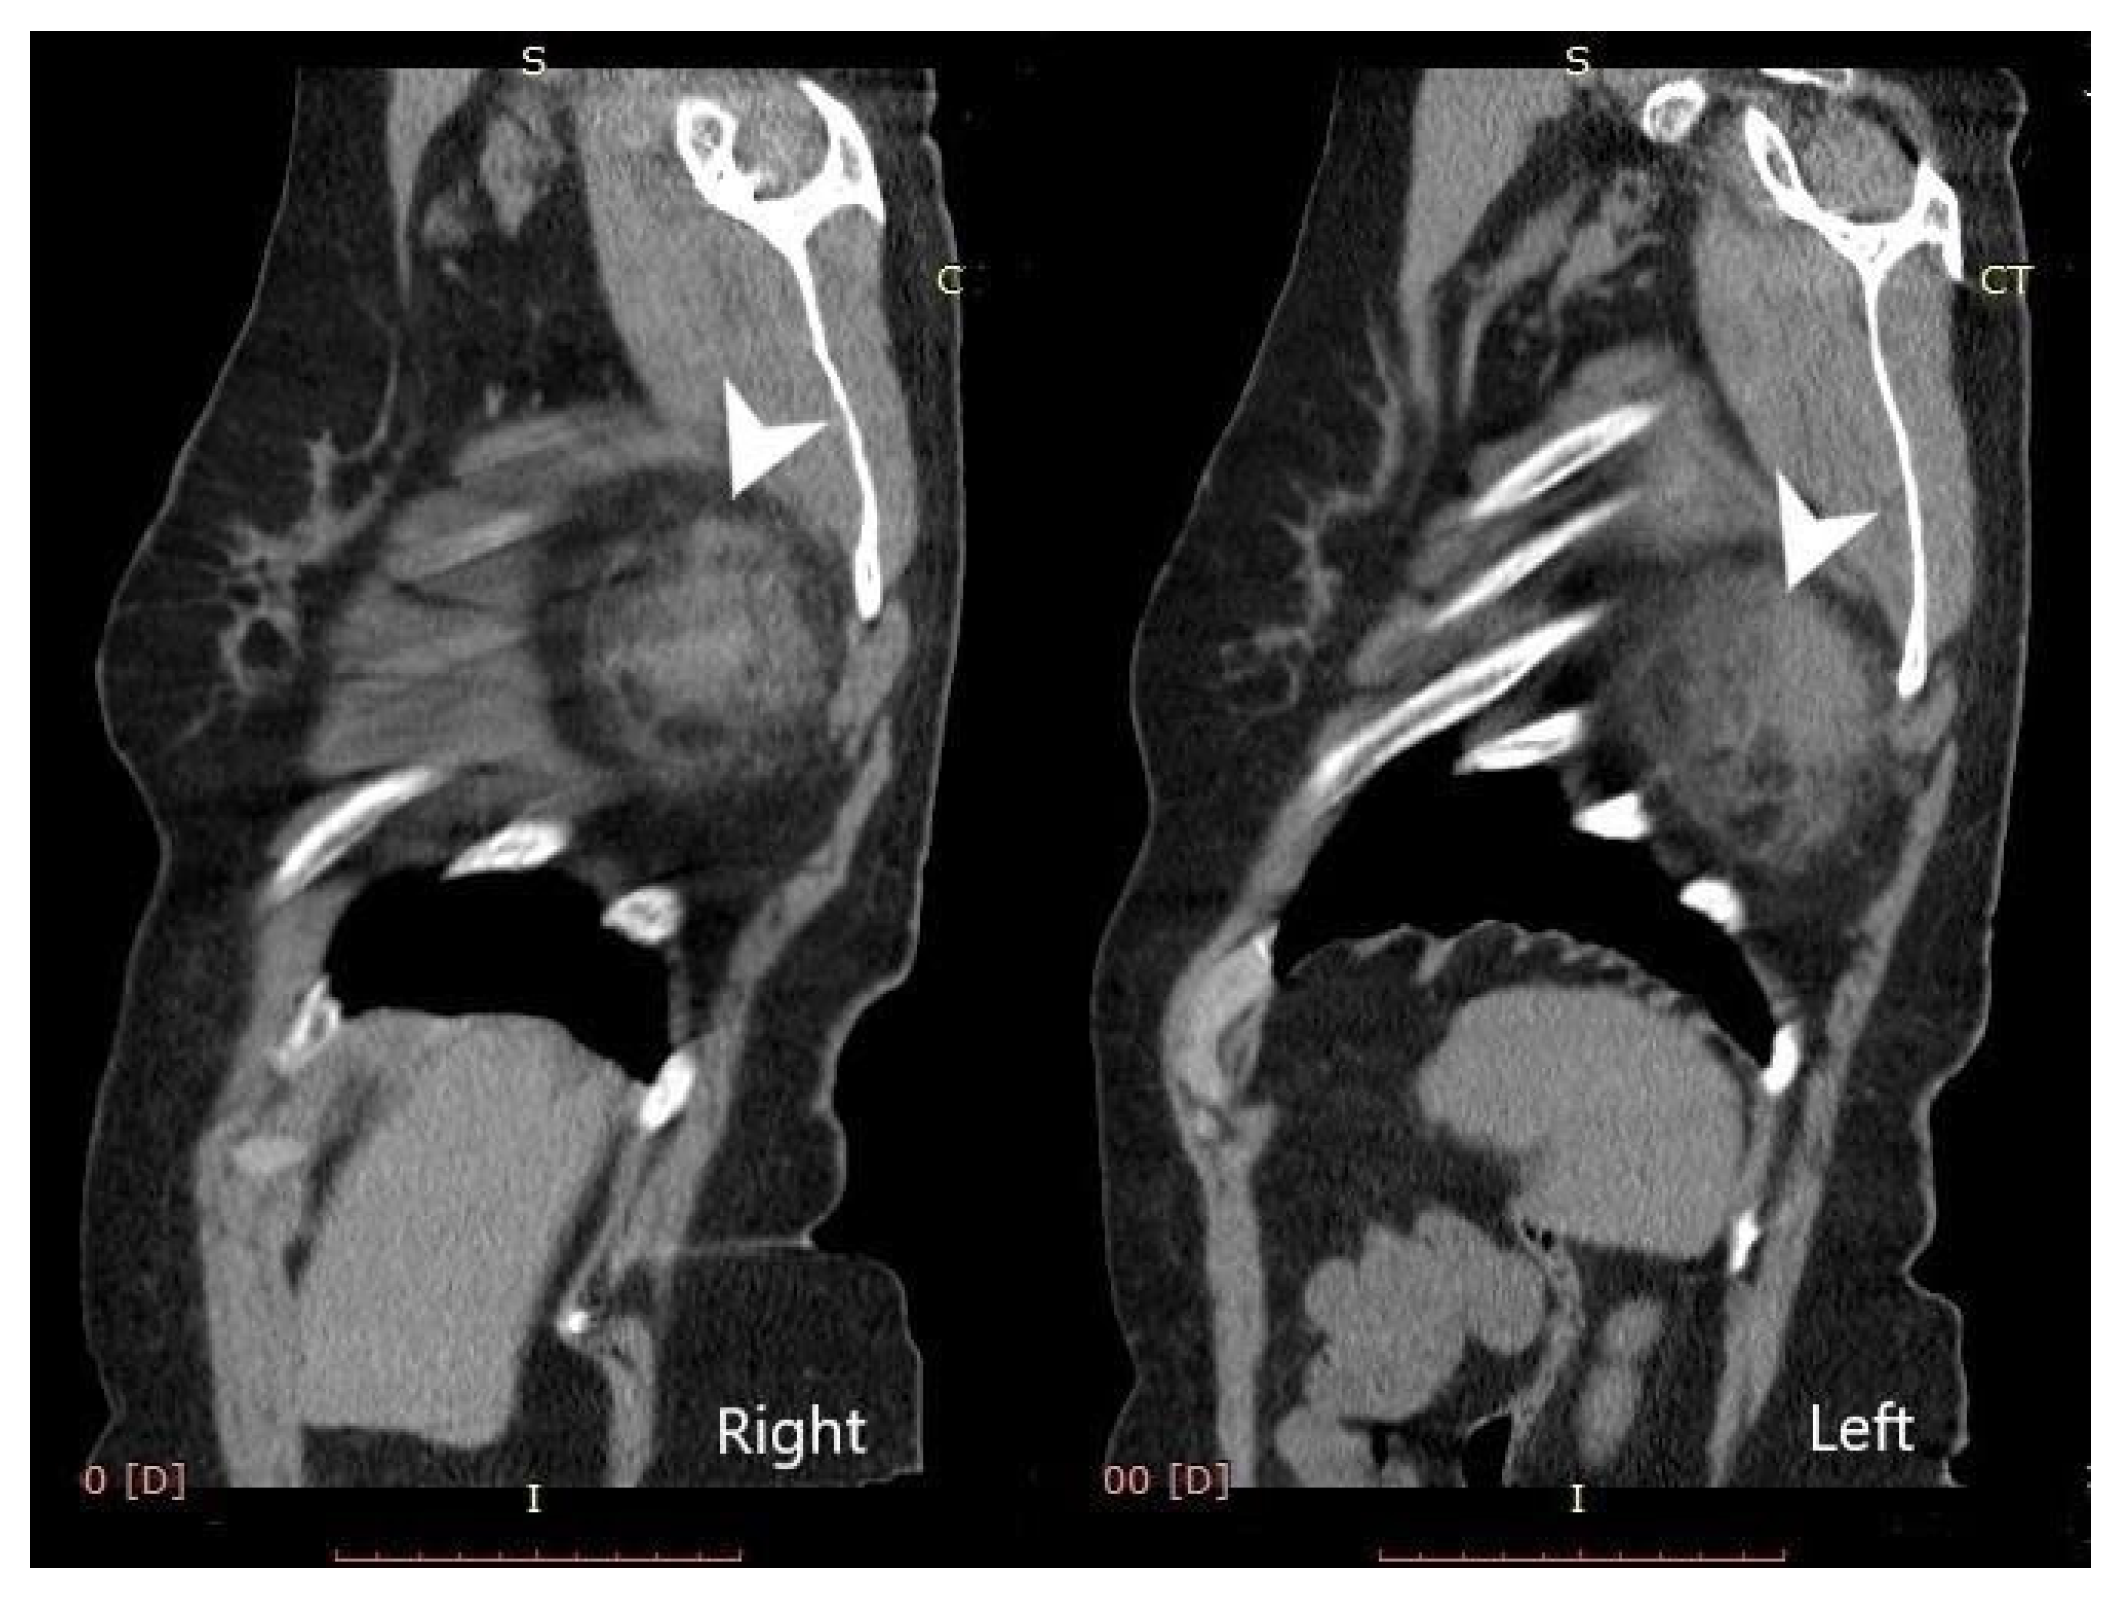

2. Case Presentation